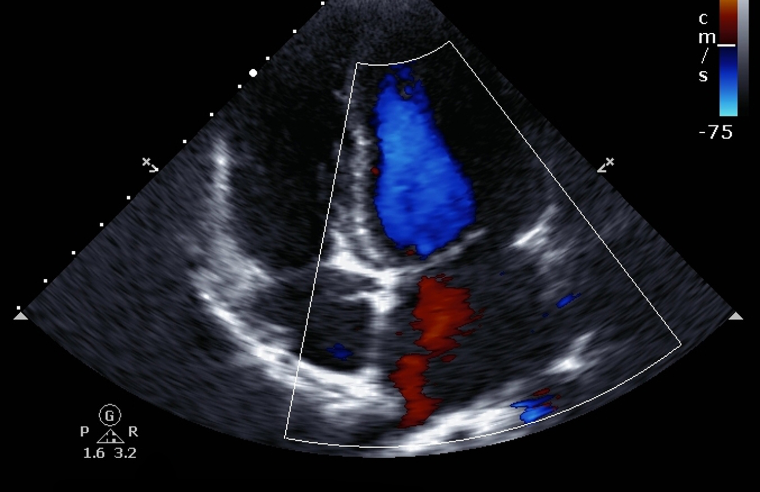

¿Qué es un Ecocardiograma Doppler Color?

El ecocardiograma Doppler es otro de los estudios del corazón más frecuentes.

Este examen permite valorar las cavidades del corazón y las válvulas cardíacas principalmente. Se miden tamaños de las estructuras, el movimiento de las paredes del corazón y como la sangre atraviesa cada una de las válvulas.

Justamente “Doppler color” es el método que permite evaluar la sangre en el corazón y vasos (arterias y venas) en el cuerpo.